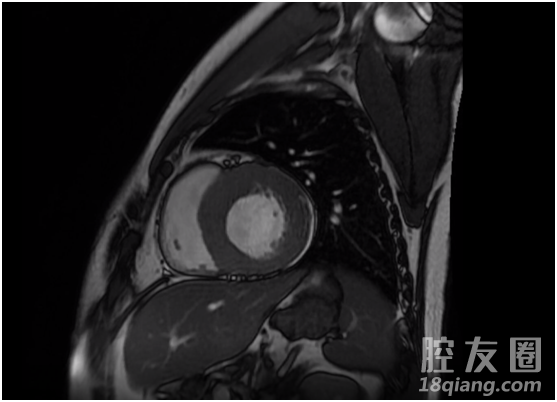

心脏核磁共振影像

临床实践表明,心脏核磁共振在诊断心肌病方面具有极大优势,心肌病是一类复杂心脏疾病,包括扩张性心肌病,肥厚性心肌病,限制性心肌病等复杂疑难心肌病,临床诊断困难,同时对患者危害极大,过去依靠心脏彩超诊断,但存在特异性差,确诊困难等缺陷,疑难患者有时甚至需要心脏活检,现在心脏核磁共振能够看到心肌异常信号影,对这些心肌病的诊断有了很大帮助。同时,心脏核磁共振对急性心肌梗死后存活心肌评价有独特优势。我院的心脏核磁共振项目,在金华地区处于领先水平,心脏核磁共振检查项目开展,对让我院心脏疾病诊治再上新台阶,可以为更多心脏病患者提供更佳服务